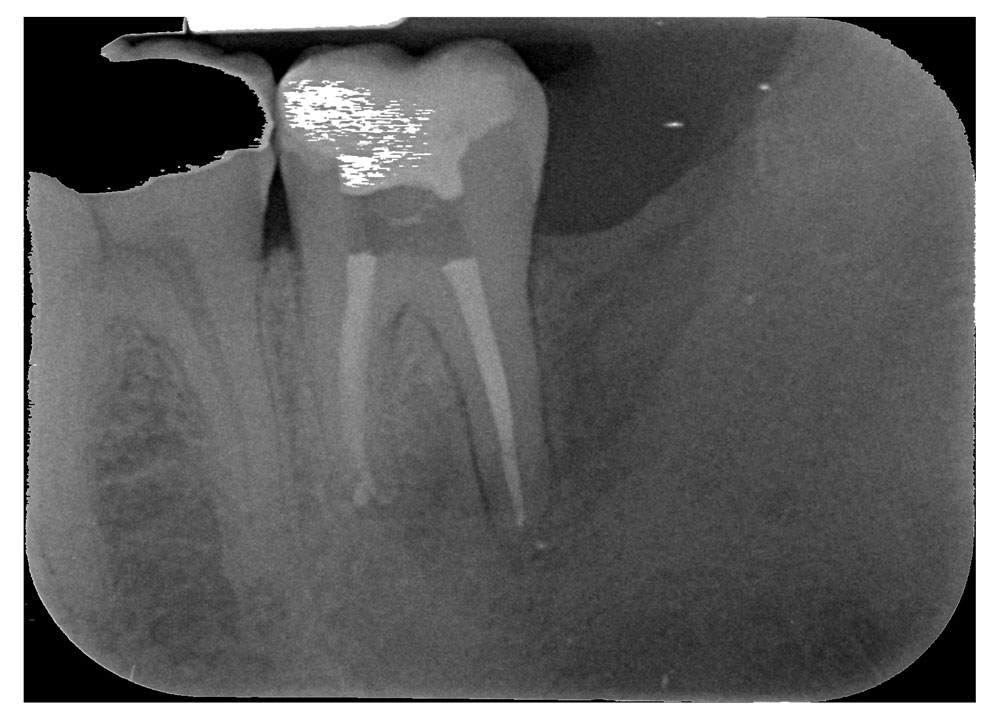

Endodonzia: è la branca che si occupa della detersione, sagomatura e otturazione dei canali delle radici dei denti.

Quando una carie penetra fino al nervo del dente è necessario intervenire devitalizzando, per prevenire ascessi dolorosi o infezioni asintomatiche (granulomi) che possono rilasciare tossine pericolose per gli organi vitali quali cuore fegato reni.

Talvolta è necessario reintervenire su devitalizzazioni precedenti in quanto non corrette e quindi fonte di possibili ulteriori infezioni.

L’esame radiografico, fondamentale per porre diagnosi in odontoiatria, in endodonzia diviene irrinunciabile perché è l’unico strumento che ci permette di “vedere” all’interno della radice del dente. È quindi molto importante la possibilità di effettuare lastre con apparecchiature digitali che emettono una dose di raggi ridotta rispetto a un radiografico tradizionale.